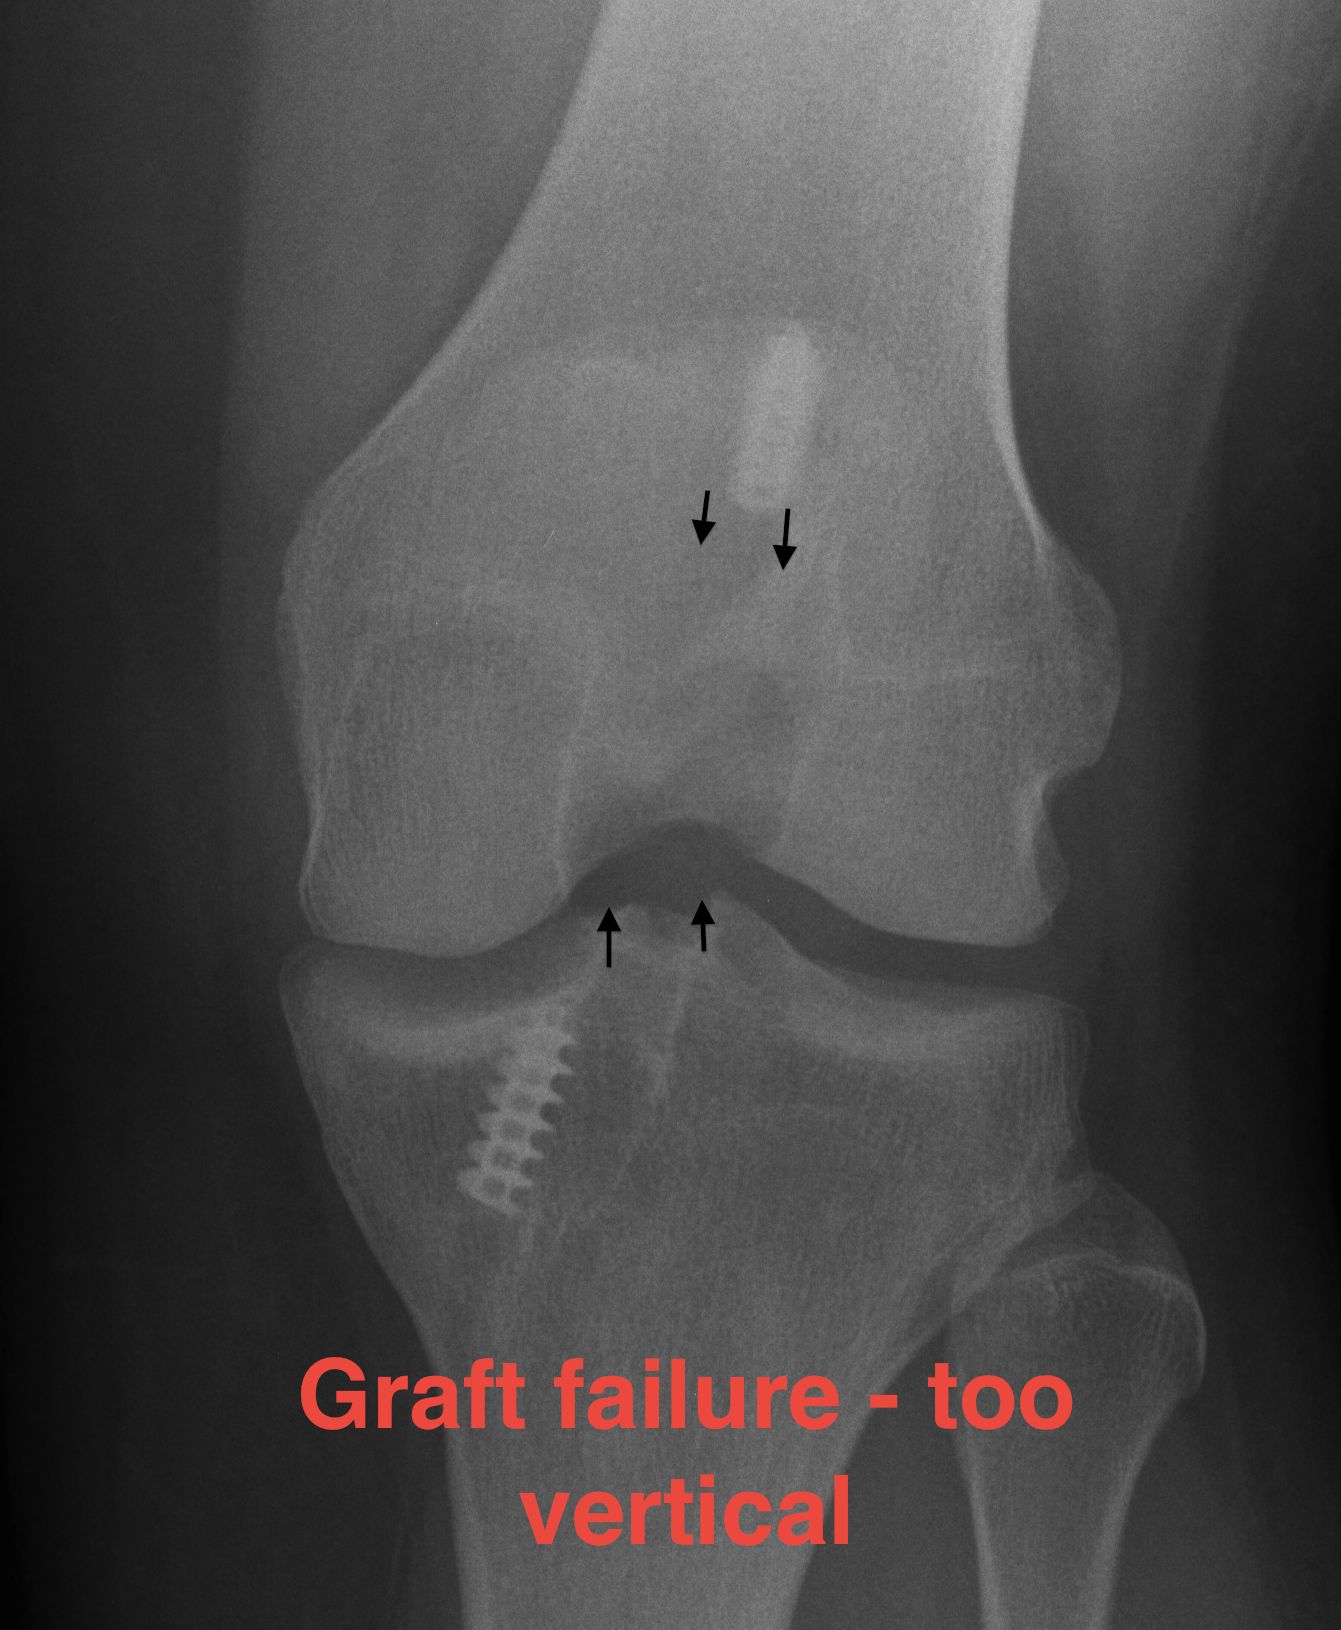

C. Superior femoral placement

- 12 o'clock position

- AP stability

- rotationally unstable / continue to pivot shift